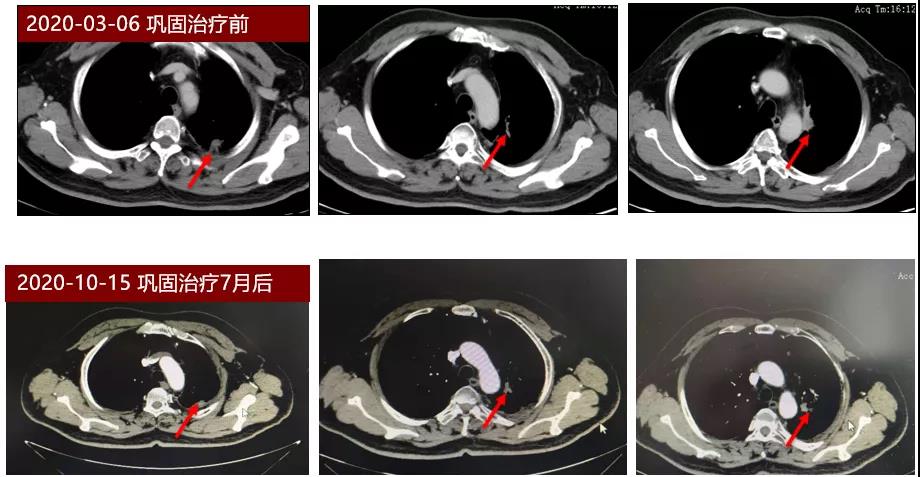

本期分享一例TNM分期为IIIB期的不可切除局部晚期NSCLC患者,初始采用重组人血管内皮抑制素联合同步放化疗进行治疗,然后以重组人血管内皮抑制素联合PD-L1单抗巩固治疗,患者初始治疗达到部分缓解(PR),同步放化疗后巩固治疗阶段病情稳定(SD),累计无进展生存期(PFS)已接近12个月。

2020年3月,患者开始使用重组人血管内皮抑制素持续泵入(30mg/d,D1-7),联合PD-L1抑制剂度伐利尤单抗(Durvalumab)联合行巩固治疗,治疗3月后复查,疗效评价SD,持续原方案巩固治疗至今,最近一次复查疗效评价仍为SD。

本例IIIB期患者起始治疗应用重组人血管内皮抑制素联合同步放化疗,实现肿瘤部分缓解,巩固治疗阶段应用了重组人血管内皮抑制素联合 PD-L1抑制剂度伐利尤单抗,达到较好的疾病控制效果,目前PFS已接近12个月,疗效已超过传统同步放化疗阶段的中位PFS,有望接近PACIFIC研究中度伐利尤单抗治疗组17.2个月的中位PFS[1]。